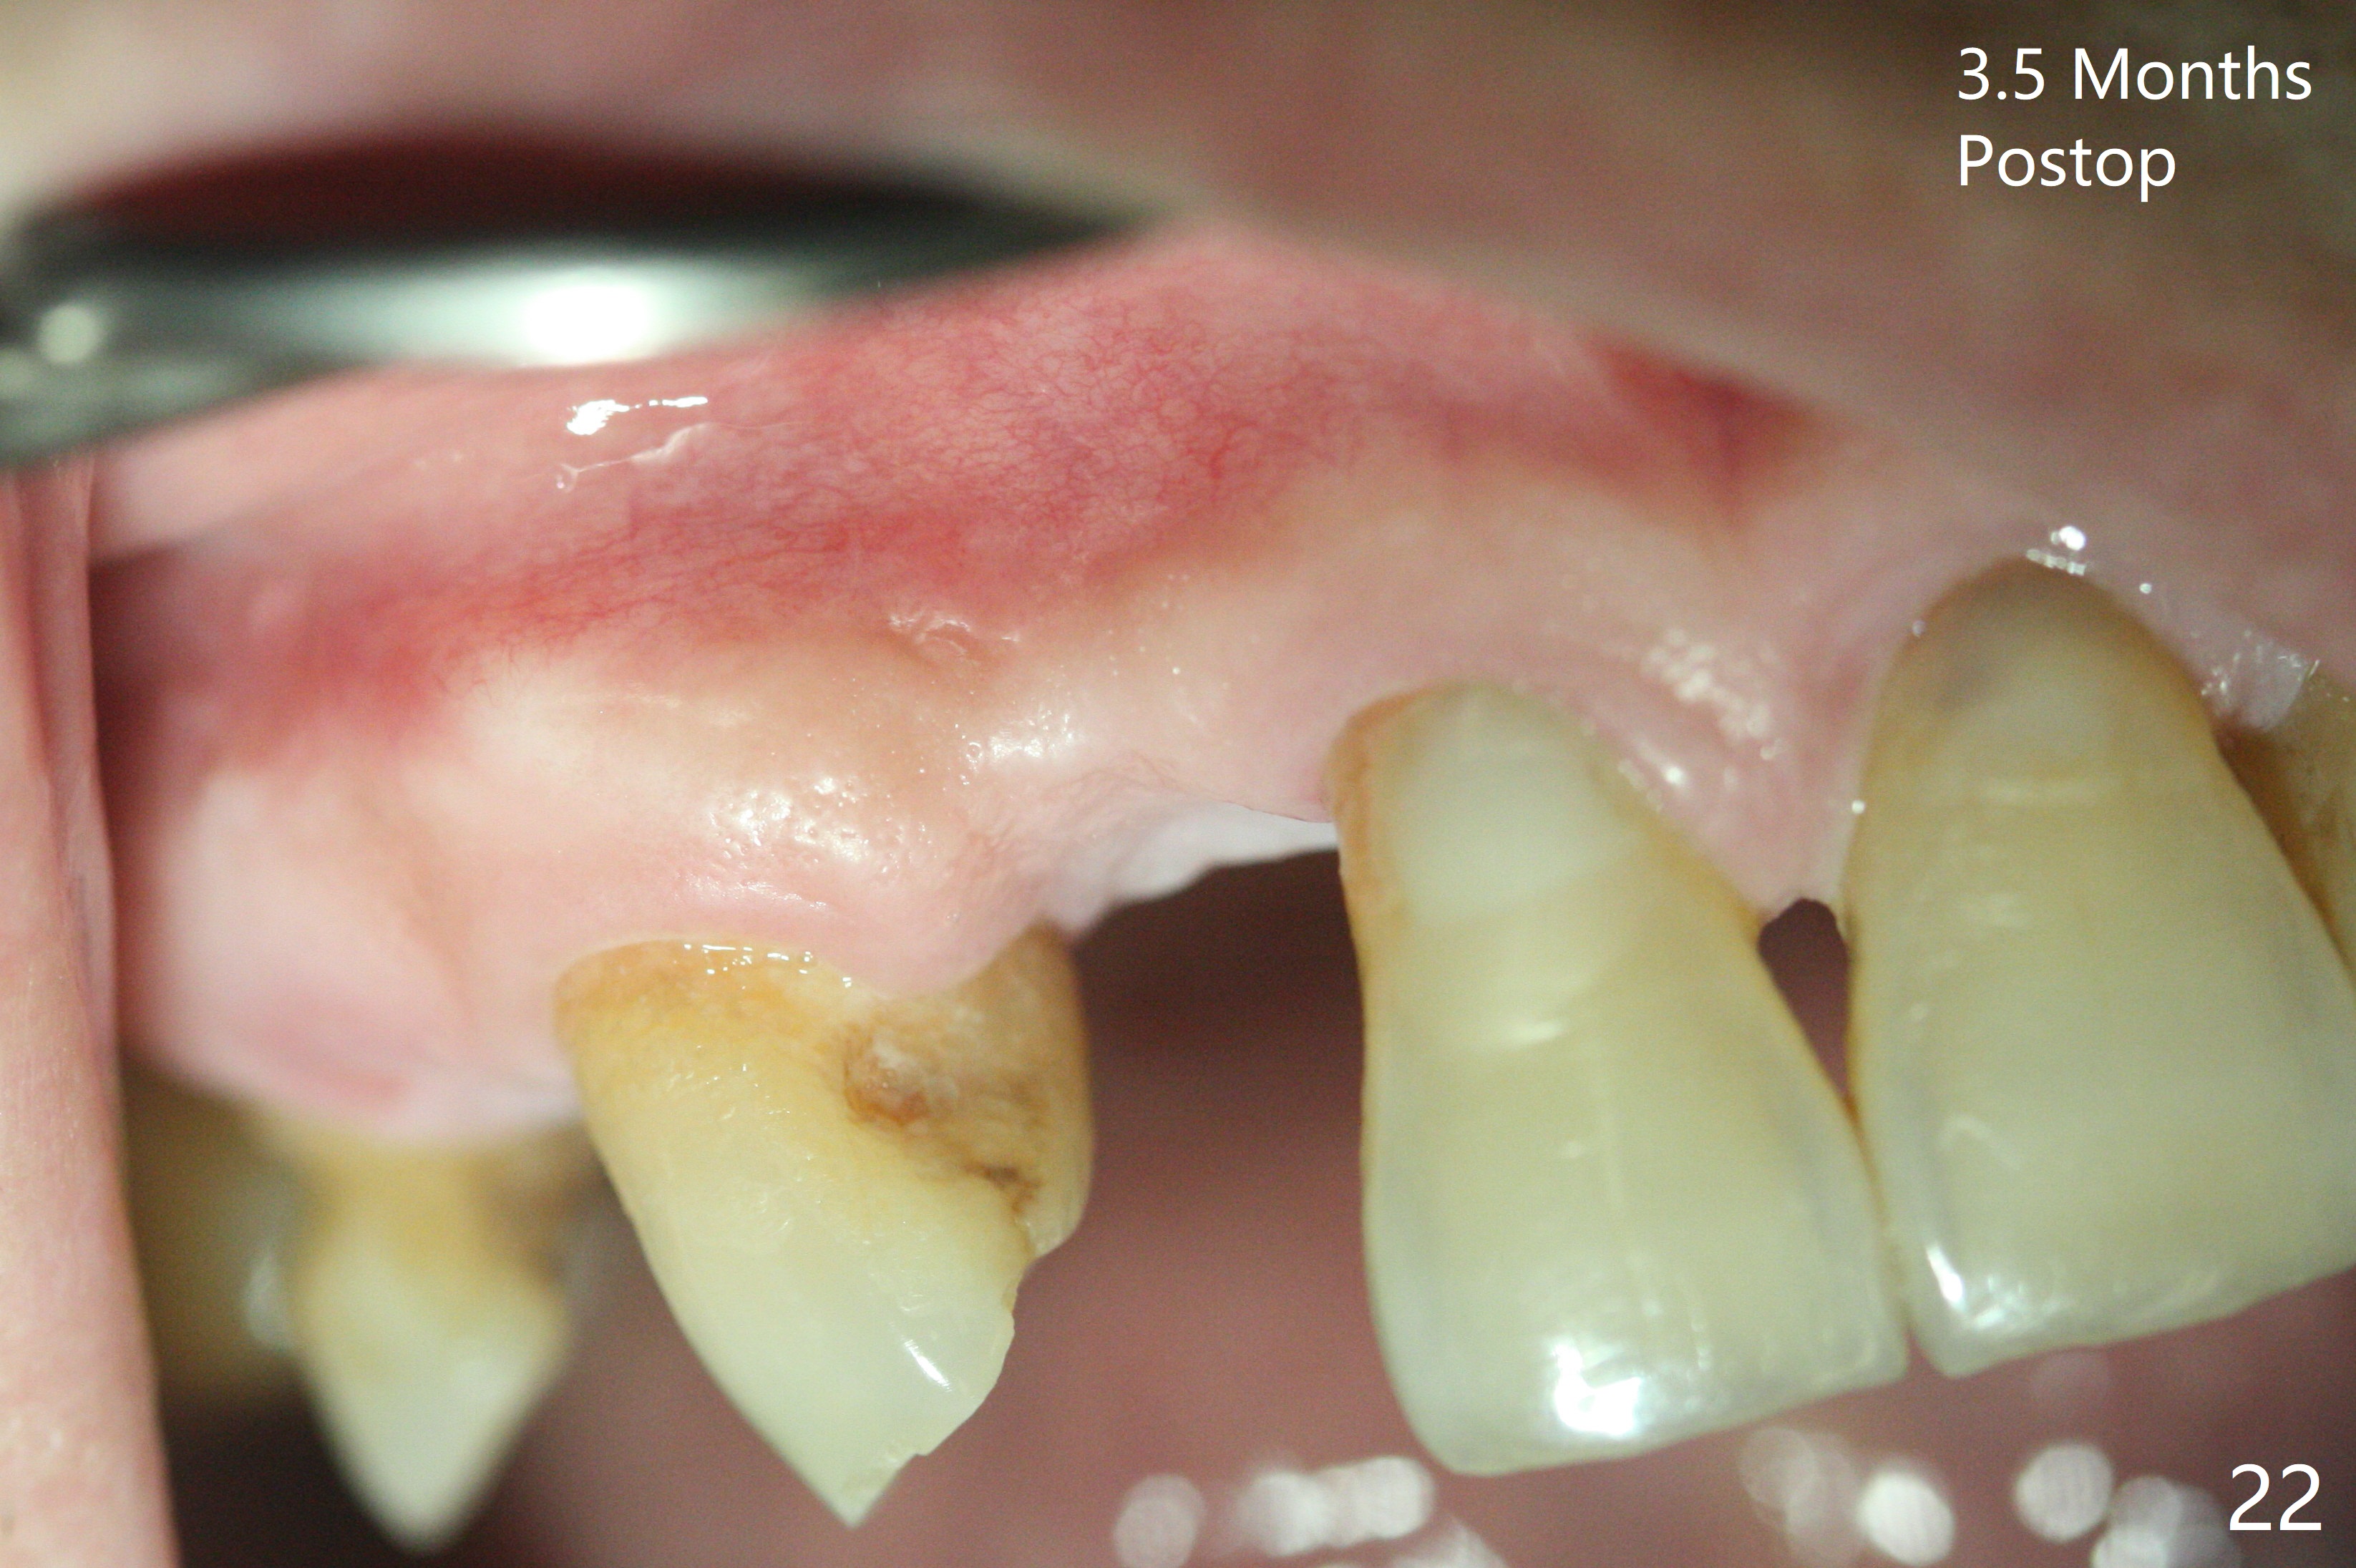

An apical abscess is present when the patient returns for immediate implant at #7 (Fig.1 *); a 2nd challenge is deep bite. After smooth extraction, the apical buccal plate is found to be perforated. Following debridement, a piece of gauze is placed in the apical defect for hemostasis, while osteotomy is initiated palatal (Fig.2). The apical defect seems to be extensive (Fig.3 yellow dashed line). A new trajectory is intended (red arrow) without much success. Before implant placement, bone graft is placed in the apical defect defect area, while a drill (Fig.4 D) is inserted in the finished osteotomy (Fig.5 O). In spite of seemingly large apical defect, the buccal crest bone exists (Fig.4 x). A 3x14(2) mm 1-piece implant is placed with stability; the first round of bone graft is apparently around the apical portion of the implant (Fig.6 *). The coronal end of the implant has to be adjusted several times buccopalatally to accommodate the deep bite. A 2nd round of bone graft following an immediate provisional closes the coronal space of the socket (Fig.7 *). CT will be taken to show the bone graft to repair the buccal plate defect when the patient returns for postop follow-up. In fact the defect is minimal in CT a month ago. The fistula does not disappear 1 week postop, but it is non tender (Fig.8). The patient complains of asymptomatic swelling in the right nostril. CT shows that the large buccal perforation is repaired with large amount of bone graft (Fig.9,10 *). It would be nicer to place the implant slightly more buccal apically (Fig.11 red lines; Fig.12 (preop design)). The buccoapical fistula disappears nearly 1 month postop (Fig.13). The apparently "lifeless" bone graft seems to be harmonious with the surrounding tissue (Fig.14). The periimplant gap reopens with implant mobility nearly 4 months postop (Fig.15), which is related to micro-movement associated with the immediate provisional. The latter is removed. A larger 2-piece implant will be placed in a 2-staged manner if needed (Fig.16). In fact the 3x14 mm straight 1-piece implant (Fig.17) has no mobility when it is retightened, but the trajectory remains buccal. Incision shows that there is no implant thread exposure. A 3x14 mm 15 degree angled 1-piece dummy implant is able to establish the correct trajectory, but there is no occlusal clearance (Fig.18). Micromovement during osteointegration may recreate loosening. Finally using Lindamann bur, the osteotomy is changed so that a 3.5x13 mm 2-piece implant does not need an angled abutment to establish occlusion (Fig.19). There is one palatal thread exposure. Allograft is placed circumferentially, followed by Human Amnion-Chorion Allograft and Collagen Plug. The wound does not heal 8 days postop (Fig.20), as related to the age (79 years old)? The wound appears to heal with a membrane on the surface (Amnion-Chorion one?) 3 weeks postop (Fig.21). The ridge looks wide 3.5 months postop (Fig.22,23). A 4.5x5.5(3) mm appears to be seated incompletely with a gap between the abutment and the implant (Fig.24<). A provisional is fabricated after heavy palatal reduction. Two months later, the provisional fractures. After repositioning the abutment with complete seating and torque (Fig.25), impression is taken. Although the buccal plate is concave, the gingiva remains healthy 10 months post cementation (Fig.26,27).